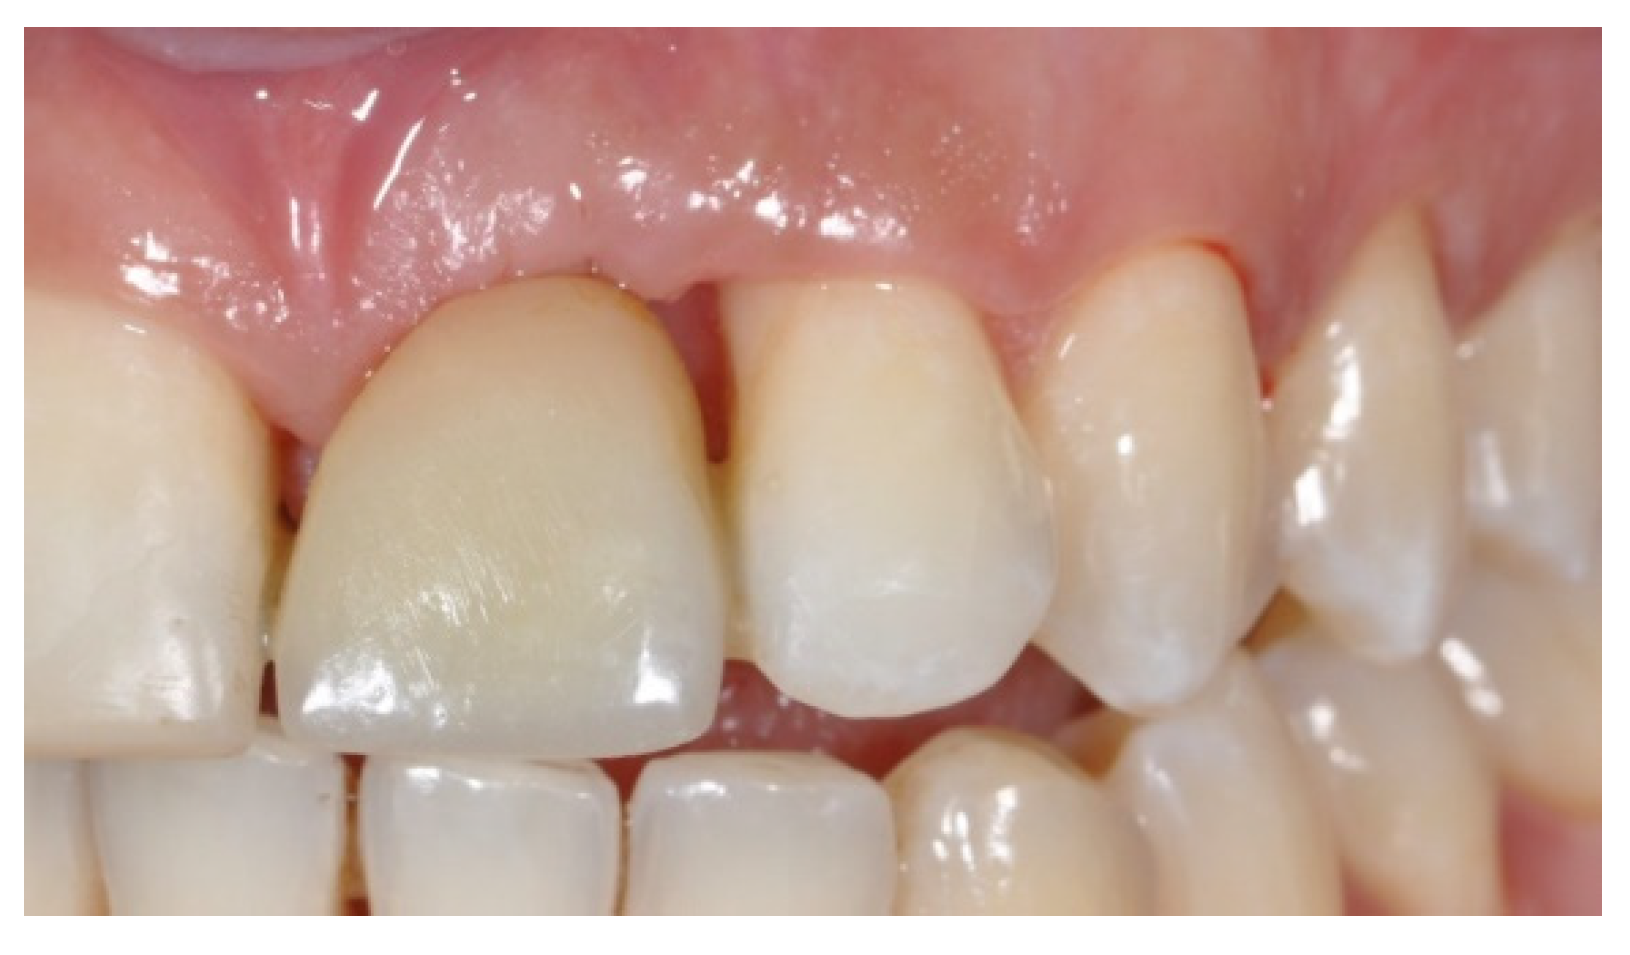

Tissue Recession around a Dental Implant in Anterior Maxilla: How to Manage Soft Tissue When Things Go Wrong?

2. Case Presentation